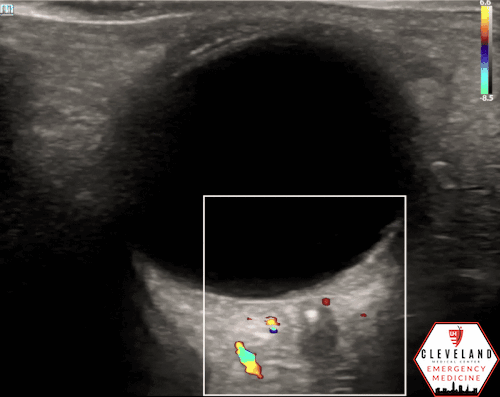

A hyperechoic focus over the distal optic nerve — referred to as the retrobulbar spot sign — has been observed on ocular ultrasound in cases of CRAO and may help differentiate it from other causes of painless monocular vision loss (7,8). Illustrated in Figures 4-6, this finding is considered highly specific for embolic CRAO and, when present, is associated with a significantly lower likelihood of temporal arteritis (9). However, its true prevalence remains unclear, and most studies evaluating its diagnostic accuracy have been small. In one study, the retrobulbar spot sign demonstrated a sensitivity of 83% and specificity of 100% for CRAO (9).

If a hyperechoic spot is identified, consider using color Doppler to assess for diminished or absent arterial flow distal to the focus (see Figure 6). Keep in mind that Doppler signal is angle-dependent, and poor probe positioning may limit its reliability.

Figure 6. Color doppler shows lack of arterial flow over the optic nerve